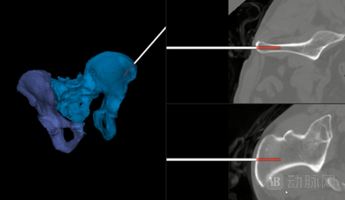

通过术前CT与术中影像的配准,首次实现对于骨折手术的三维导航,全面提升骨折手术的精度和安全性。

精确实施复位规划结果,计算复位路径,降低复位负载需求,复位操作误差<2mm。

术前无创,毫米级术中跟踪误差,毫秒级跟踪延时,三维模型及任意方向的CT层切。